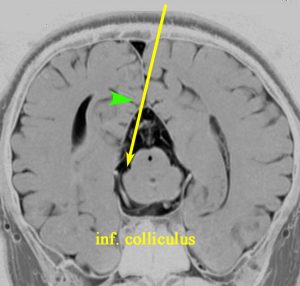

5. 後交連 PC posterior commissure

松果体腫瘍が上丘を圧迫して眼球運動障害を呈することは良く知られています。実際に松果体腫瘍の手術で上丘を損傷することはほとんどなく,術後に残る微妙な複視は,後交連 (PC posterior commissure) の損傷によって生じます。左の画像のように,松果体腫瘍が第3脳室方向に伸展増大すると後交連を圧排して,後交連は扁平化します。手術中には,上丘の奥に,上丘と連続して白く薄い脆弱な白質組織が見えます。それが後交連です。左右にも長い白質組織なので,腫瘍底面から非常に慎重に剥離する必要があります。後交連の剥離が終わると第3脳室内の髄液腔に抜けます。

左の図は,眼球運動に関わる中枢と神経を表したものですが,PTAの手術で損傷するのは,PC 後交連とSC 上丘くらいなもので,上丘は丈夫な組織なので,術後合併症である複視は後交連損傷であることが多いのです。